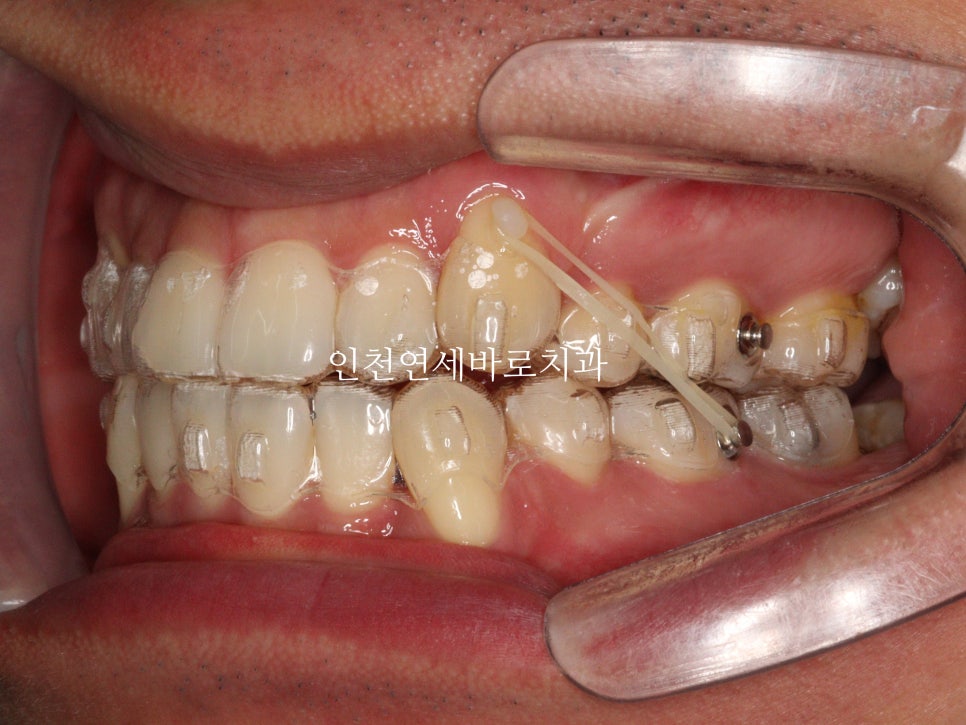

하이캐나인 이라고 불리는

위쪽 높이 위치해있는 송곳니의 교정치료의 경우, 많은 경우에 고무줄이 추가로 필요합니다.

인비절라인 자체도 열심히 껴야하지만,

이 환자분의 경우에는 12시간 정도 고무줄도 함께 착용했습니다.

약 7개월이 지난 후의 사진인데 벌써 많은 양의 덧니가 해결되었네요